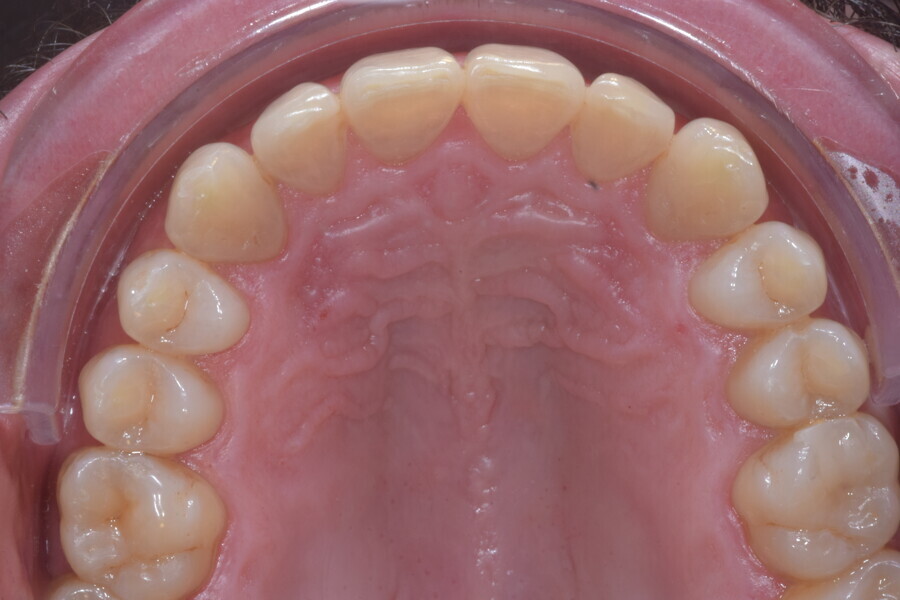

At the end of the treatment, Class I canine and molar relationships were obtained, maxillary incisor inclination was slightly increased (Ui–FH = 112°), mandibular incisor inclination (IMPA = 97.09°) was fully corrected by means of proclination and the divergency was slightly increased (SN–GoGn = 27°) because of the relative posterior extrusion and use of Class II elastics—a small variation (1°), which is interesting considering the age of the patient (Figs. 25–35). A balanced smile arc was obtained with an ideal relationship between the maxillary incisors and lower lip, and torque control of the lateral and posterior segments generated a broader smile.

At the one-year follow-up in retention (Vivera retainers with bite ramps, Align Technology), the result was stable and intercuspation was improved (Figs. 38–42).